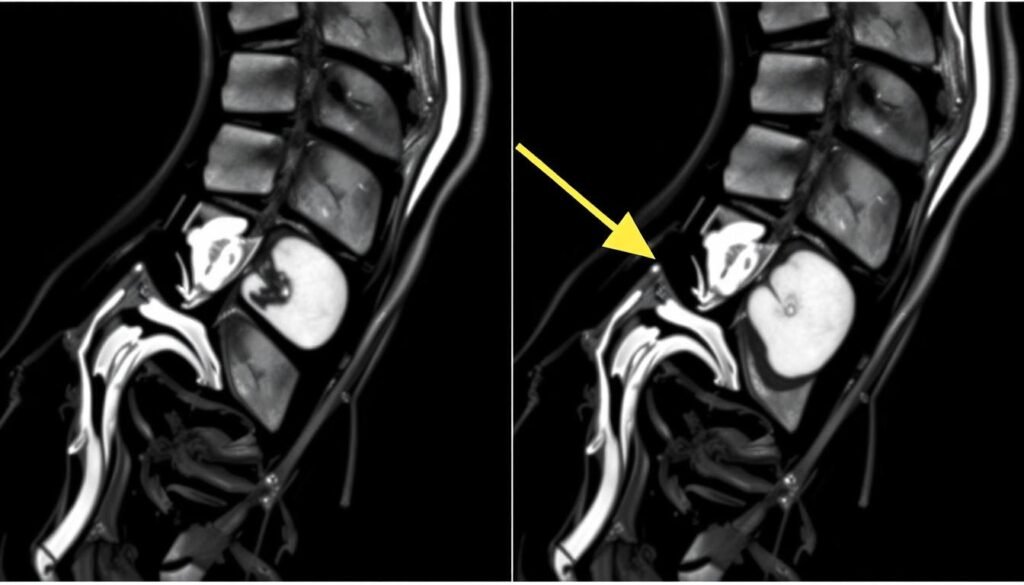

Bildgebende Verfahren

Zur genauen Diagnose kommen verschiedene bildgebende Verfahren zum Einsatz:

- Magnetresonanztomographie (MRT): Die bevorzugte Methode, da sie Weichteile wie Bandscheiben und Nerven sehr gut darstellt.